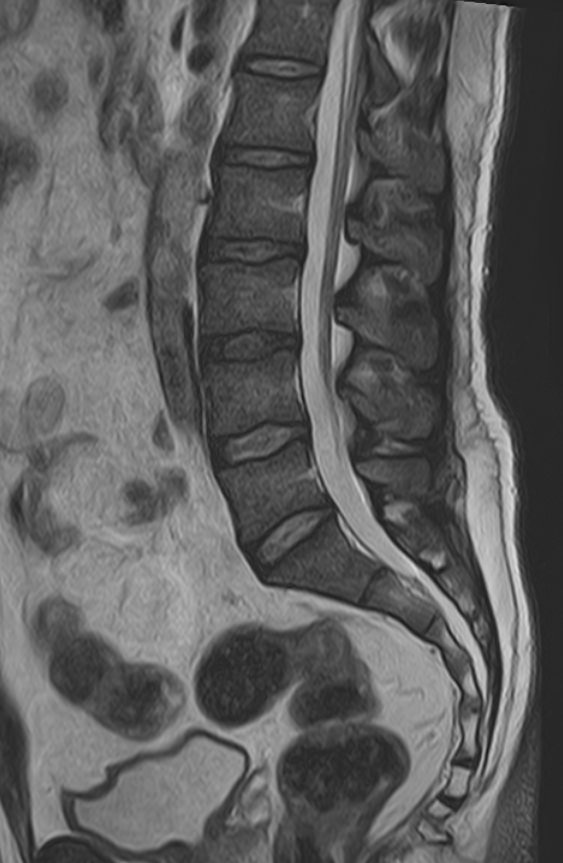

Магнитно-резонансная томография является наиболее чувствительным и эффективным методом диагностики дегенеративно-дистрофических заболеваний, травматических, воспалительных изменений, а также опухолевых процессов позвоночника. Метод позволяет оценить состояние структур позвонков, позвоночного канала с расположенным в нем спинным мозгом и окружающих мягких тканей, кроме того является основным способом диагностики демиелинизирующих заболеваний спинного мозга.

В клинике Доступная медицина установлен новейший высокопольный томограф экспертного класса TOSHIBA VANTAGE TITAN 1,5 Тесла, на котором выполняется комплексное обследование позвоночника. За счет высокой напряженности магнитного поля аппарат при сканировании создает изображения на плоскости превосходной четкости, затем с помощью компьютерных приложений данные преобразуются в изображения трехмерного формата, что обеспечивает точность и достоверность диагностики.

При подозрении на распространенный процесс с поражением различных уровней позвоночника в клинике «Доступная медицина» возможно проведение комплексной МРТ позвоночника – 3 отдела.